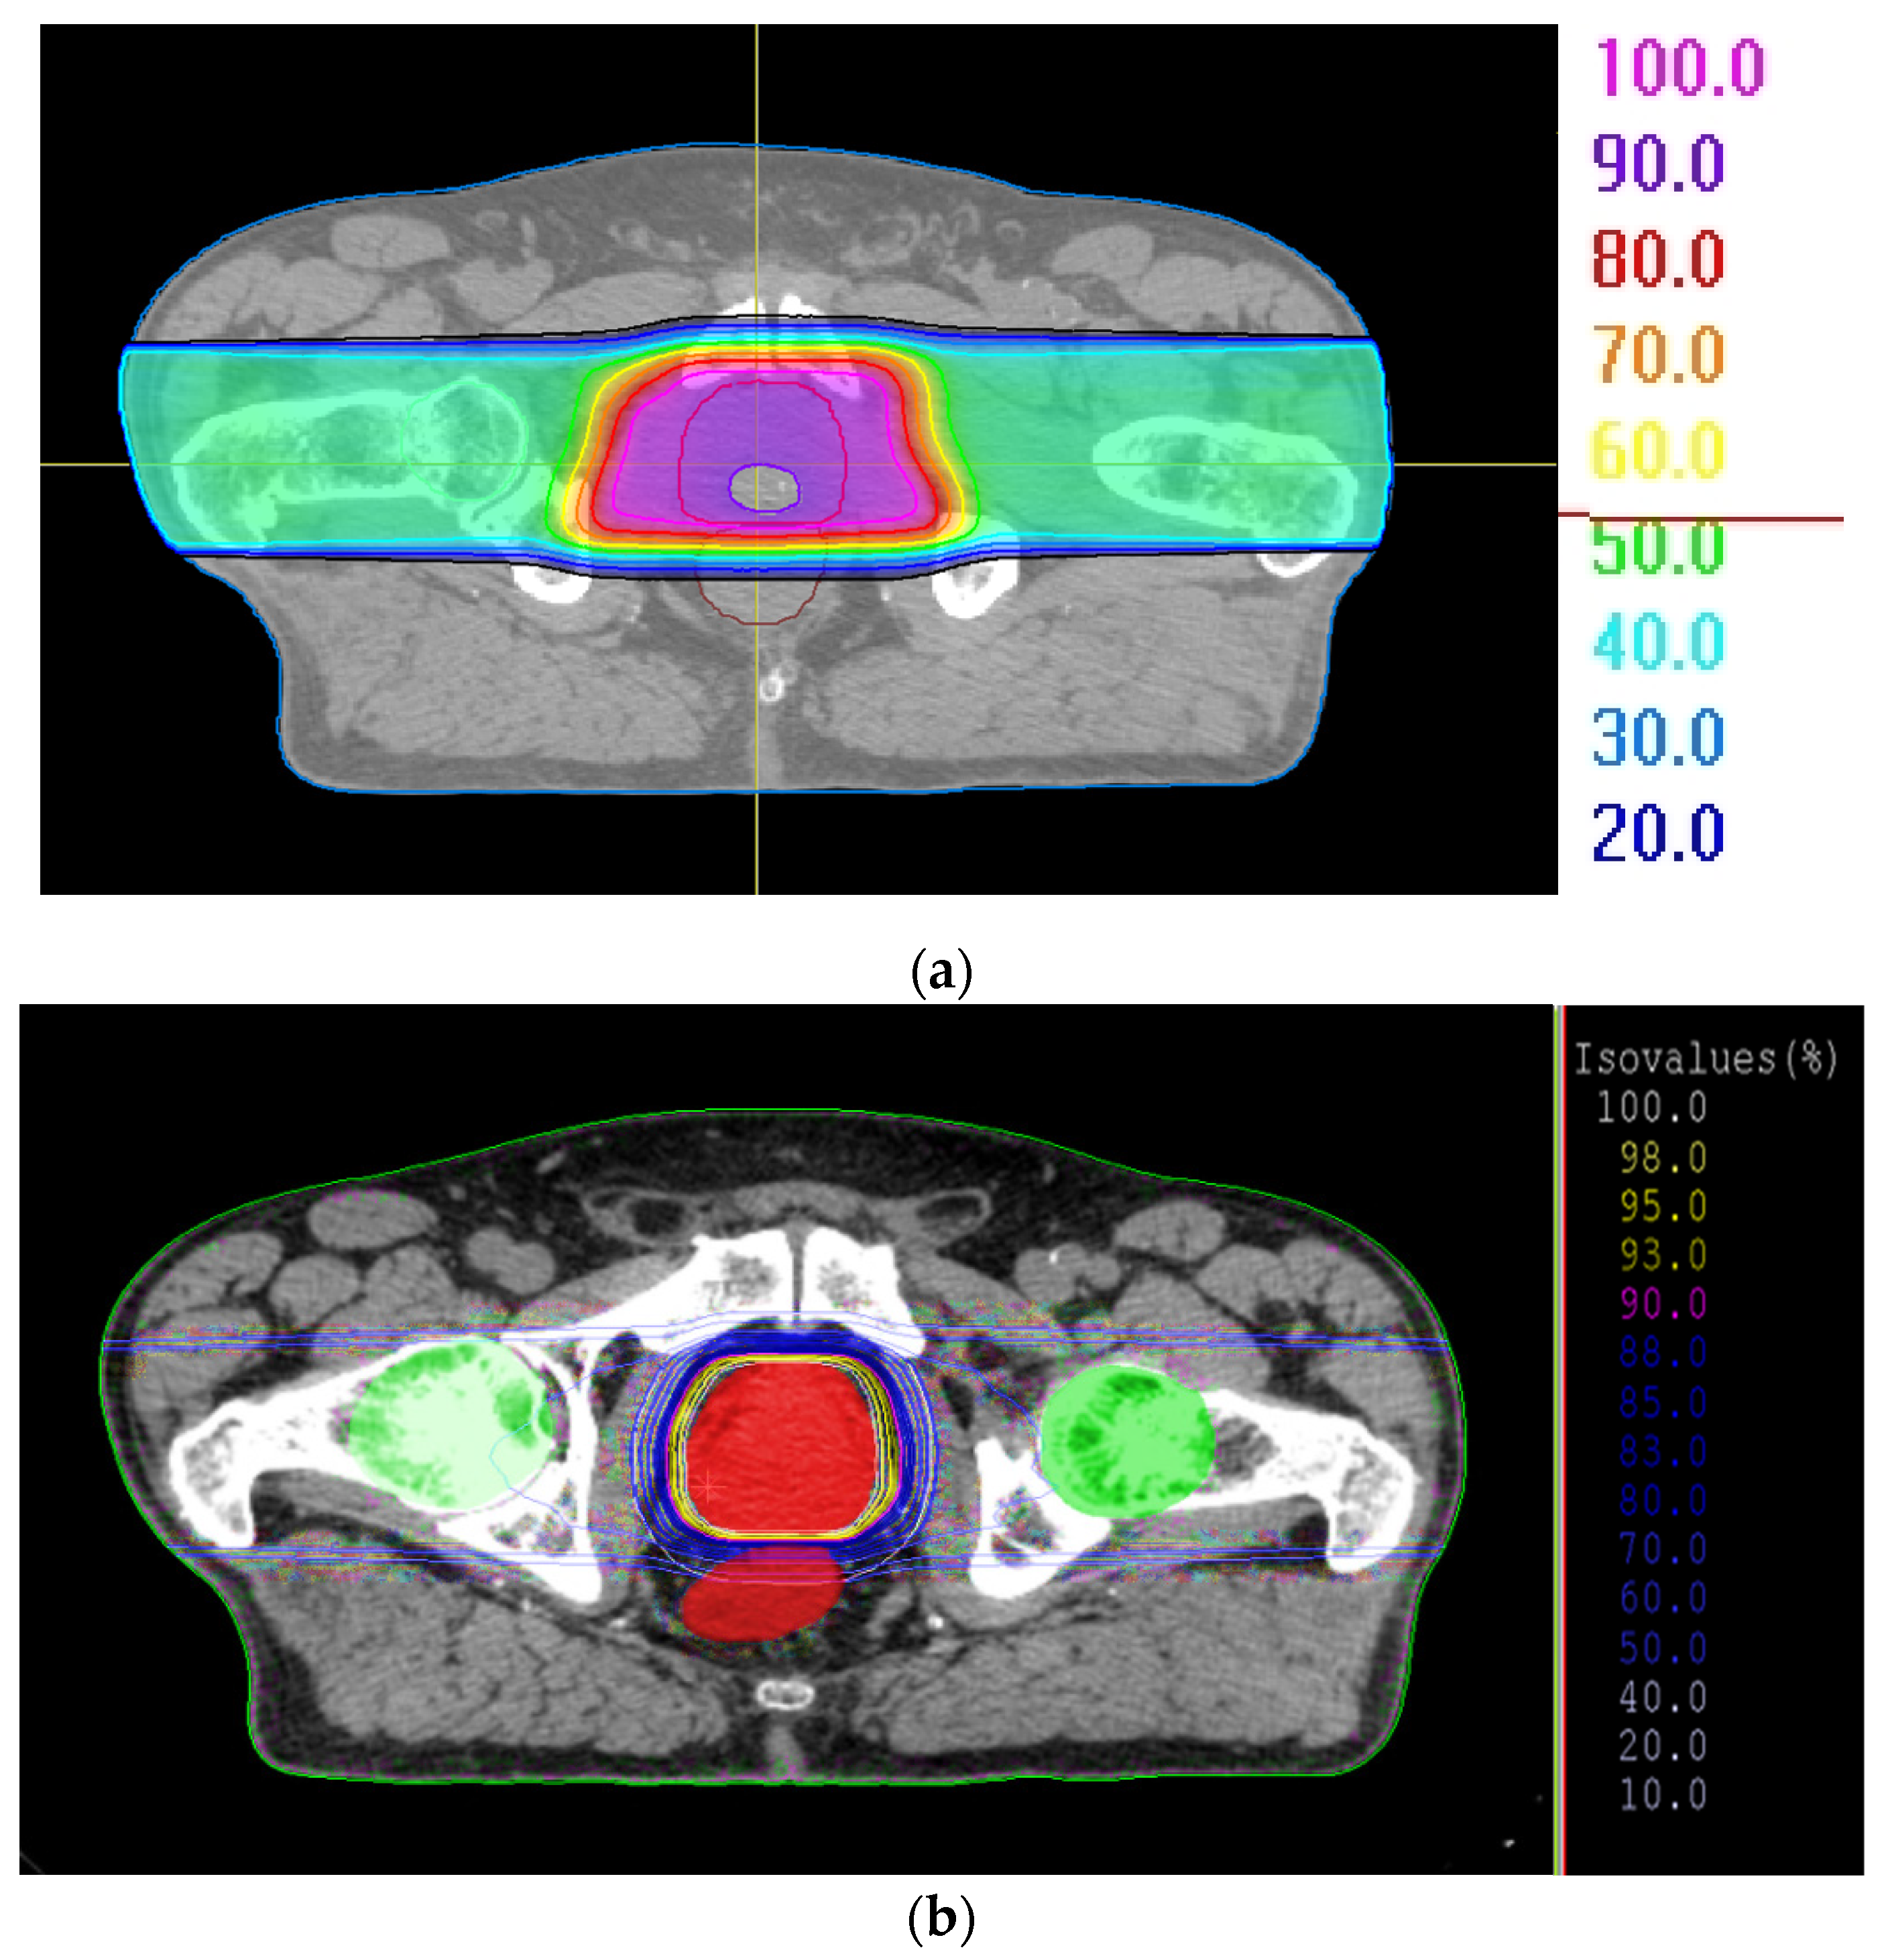

2.2. Treatment Plans